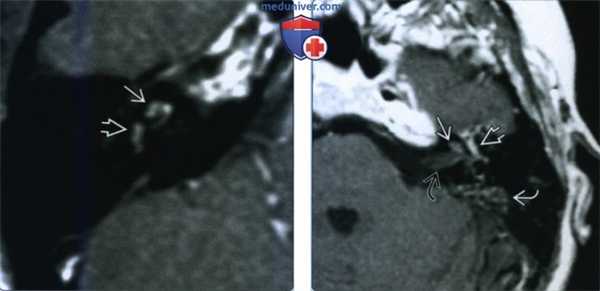

(Слева) При аксиальной МРТ Т1ВИ определяется минимальный гиперинтенсивный сигнал в преддверии и улитке у пациента с вестибулокохлеарной шванномой.

(Справа) При аксиальной MPT Т2ВИ визуализируется материал с сигналом, соответствующим мягким тканям, замещающий сигнал, типичный для нормальной жидкости в преддверии и улитке у пациента с ИЛШ вестибулокохлеарного типа. Эти опухоли чаще распознаются на МРТ высокого разрешения (Т2) в условиях высокой настороженности.

(Слева) При аксиальной МРТ Т2 ВИ определяется ИЛШ трансмакулярного типа в виде материала с интенсивностью сигнала, соответствующей мягким тканям, заполняющего преддверие и распространяющегося вдоль ветвей преддверного нерва до дна дистальных отделов внутреннего слухового канала (ВСК).

(Справа) При аксиальной МРТ Т1ВИ у этого же пациента определяется контрастное усиление интравестибулярной и дистальной интраканаликулярной части этой трансмакулярной шванномы. Минимальное отличие параметров контрастного усиления обусловлено эффектом усреднения объема.

(Слева) При аксиальной МРТ Т1ВИ С+ определяется контрастное усиление дна дистального ВСК и улитки (ИЛШ трансмодиолярного типа). Опухоль растет из улитки через стержень и канала улиткового нерва, достигая дна ВСК.

(Справа) При аксиальной МРТ Т1ВИ С+ визуализируется крайне редкая ИЛШ трансотического типа. Обратите внимание, что опухоль, накапливающая контраст, распространяется через ВСК из ММУ, а также поражает внутреннее и среднее ухо.